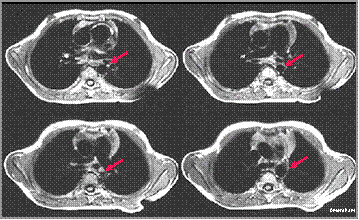

Axial spin-echo MRI-Coarctation of the Aorta